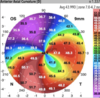

Quais as características topográficas do ceratocone?

Astigmatismo irregular e assimétrico

Aumento da curvatura inferior

Índice I/S ≥ 1,4

O que é o índice I-S na topografia do ceratocone?

O I-S corresponde à divisão da ceratometria de 5 pontos inferiores e 5 pontos superiores nos 3 mm centrais da córnea. Se ≥ 1,4 sugere ceratocone.

Quais os achados tomográficos do ceratocone?

Abaulamento inferior

Ilhas descentradas de aumento da elevação anterior/posterior

Afilamento da córnea coicidindo com área de abaulamento/elevação

Índices de progressão paquimétricos acentuados

Quais são os criterios de Rabinowitz para diagnóstico do ceratocone?

K ≥ ou igual a 47,2

I-S ≥ ou igual a 1,4

S RAX > 21º

A presença de 1 critério tem sensibilidade de 98% no diagnóstico do ceratocone

O que é o índice de Roush para o diagnóstico de ceratocone?

Diferença > 100 µm entre o ponto mais elevado e o menos elevado nos mapas de elevação anterior ou posterior